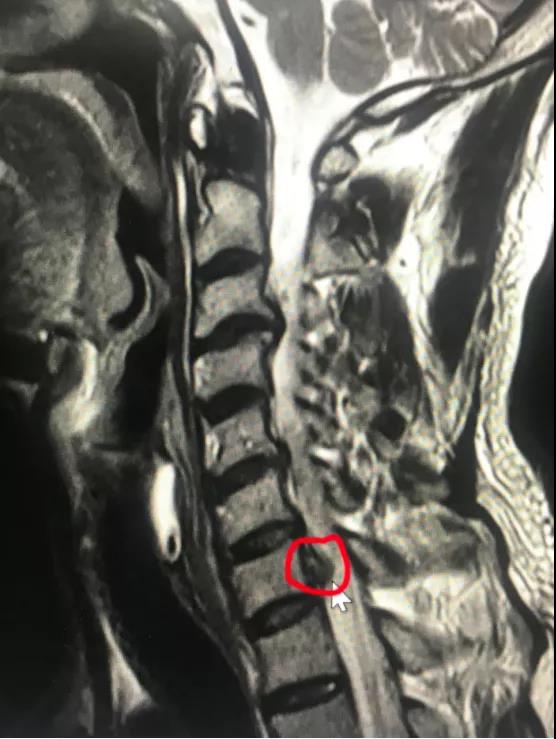

颈椎前路间盘摘除椎管减压植骨融合内固定(ACDF)是经典的手术方式,但要牺牲一个颈椎运动节段。近日,*安泰**市中心医院脊柱外科收治宁阳患者张某,45岁,颈部不适2月,右上肢疼痛麻木1月余。采用牵引、药物等治疗,效果欠佳。疼痛无法缓解,严重影响睡眠。入院诊断颈椎间盘突出症,完善X线、CT、MR相关检查显示:颈6/7椎间盘突出,向下方脱垂至颈7椎体中下方,压迫脊髓。由于颈椎椎间盘突出高度脱垂,至椎间隙下方较远,采用传统ACDF,从前方椎间隙根本无法取出脱垂的间盘组织。科室采用局部麻醉,颈椎后路“钥匙孔”技术,通过在颈7右侧椎板用高速磨钻磨出一个7毫米的小孔,直达病变部位,将高度脱垂的间盘顺利取出,患者术后疼痛即刻消失,由于局部麻醉,增加了手术的安全性,患者术后就能够正常下床活动,手术第2天出院,受到了患者及家属的好评。

神经根型颈椎病是最常见的颈椎病类型,由于颈椎神经根活动度较小,“黄豆”大小的的颈椎间盘突出就可以引起剧烈疼痛,脊柱外科开展脊柱内镜治疗颈椎间盘突出技术(“钥匙孔”技术)已经有3年时间,具有“三好一满意”(1、外观好,颈部后方只有7毫米切口,一般愈合以后看不到切口;2、内镜下视野好,放大约4-10倍,清晰,完全不破坏脊柱稳定性,不需内固定,微创,安全;3、疗效好,通过透视定位,直达患处,直接解除神经压迫;4、患者满意,术后即刻解除症状,早期下地,早期恢复工作生活。)的优势。脊柱外科通过此技术已治愈近100例患者,都收到取得良好的治疗效果。该患者高度脱垂型的颈椎间盘突出采用内镜下颈椎后方椎板“钥匙孔”技术,是在掌握熟练的颈椎内镜技术的情况开展的,此手术的成功开展,标志着*安泰**市中心医院脊柱外科颈椎内镜技术又跨上一个新的台阶。